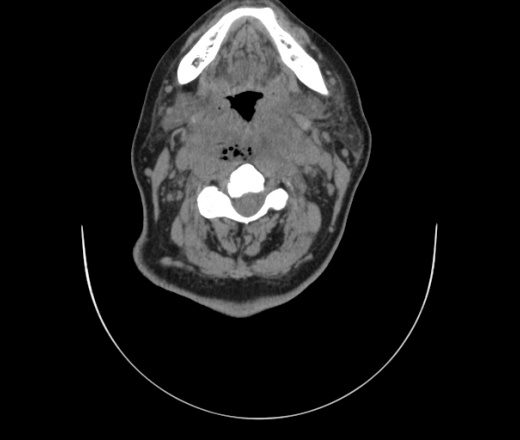

Женщина поступила в х/о спустя 4 дня после того как при употреблении карася подавилась костью.

Наличие газа в средостении на протяжении тел С2-С6 (медиастинальна эмфизема); рыбная кость на уровне тела С6.

При всем уважении, но говорить о медиастинальной эмфиземе, оценивая мягкие ткани шеи, как-то слишком резко. На мой взгляд, это ретрофарингеальное пространство.

Эвакуировали почти 100мл гноя. Но кость не смогли найти. Думаю что она даст дальнейшее ослоднение. Эндоскопически за черпалонадгортаной звязкой не смогли зайти в пищевод, все мягкие ткани отечные, просвет пищевода сдавлен. По всей видимости параэзофагеальная клетчака тоже задействована. Эмпиема, если ее можно так назвать, незнаю как правильно дошла до уровня яремной вырезки. Чем закончиться напишу. Ждем медиастинита.

Флегмона заглоточного пространства шеи, только операция, флегмоны вскрывают. Риск медиастинита.

Согласен с Вами; конечно, наличие газа в клетчатке ретрофарингеального пространства (затмение с опечаткой..). К сожалению, процесс "продвигается" к медиастиниту. Но почему никто, не отмечает наличие рыб. кости; или это для Всех очевидно?

Так вы уже отметили. Хотя ориентировал бы не скелетотопически, а на перстнечерпаловидный сустав.

Кость то мы сразу выявили, размеры где то 17*2мм, но ее так и не получается найти в этой каше